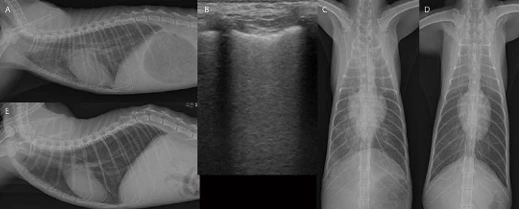

image.png?type=w966

8살 중성화 수컷 5.6kg Persian 고양이가 2일 전부터 급격한 기력 저하, 식욕 감소 증상으로 내원하였습니다. 평소에도 오심 증상이 잦았다고 합니다. 흉부방사선에서 Severe globoid cardiomegaly가 관찰됩니다(A, D). 심음영 내로 장분절 음영이 관찰되기 대문에 바로 PPDH(Peritoneopericardial diaphragmatic hernia) 상태를 고려할 수 있습니다. PPDH 환자에서 심초음파 검사를 하면 일반적으로 심장 옆에 간엽이 잘 관찰되는 편입니다. 그러나 이 환자의 경우 심장 주변으로 지방 및 장 분절만 관찰됩니다. 복부초음파 검사에서 횡격막 스캔 시 간엽 및 담낭이 herniation되어 관찰되는데, 간엽이 작고 울퉁불퉁하며 다수의 myelolipoma (혈관 신호 없는 균질한 고에코성 결절성 음영) 소견이 관찰됩니다(J). CT 검사에서 간엽, 담낭, 소장 분절이 herniation되어 있는 PPDH로 확인됩니다. 초음파 소견과 유사하게, herniation되어 있는 간엽은 심음영이 맞닿아 있지 않고, 작고 울퉁불퉁하며, 다수의 myelolipoma 소견이 관찰됩니다(B, C, E, F, G). PPDH 수술적 교정(H, I) 이후, 환자는 잘 회복하였고, 현재 특별한 임상 증상 없이 모니터링 중입니다.

여기서 잠깐 비교증례!

< PPDH >

3살 중성화 수컷 4.1kg Scottish fold cat이 간헐적인 구토 증상으로 내원하였습니다. 위 환자처럼 흉부방사선 검사에서 Severe globoid cardiomegaly가 관찰됩니다(A, C). 심음영 내로 장분절 음영이 관찰되기 대문에 바로 PPDH를 고려할 수 있습니다. 초음파 검사에서 herniation된 간엽이 작고 울퉁불퉁하며 다수의 myelolipoma 소견이 관찰됩니다(J). CT 검사에서 pericardium 내부로 간엽(quadrate, right medial and left medial lobe), 담낭, 소장 대부분, 대장 일부분, 장간막의 herniation이 관찰됩니다. PPDH로 인한 심장의 압박 및 좌측 두측 변위가 확인됩니다. 초음파 소견과 유사하게, herniation되어 있는 간엽은 작고 울퉁불퉁하며, 다수의 myelolipoma 소견이 관찰됩니다(B, D-I). 위 환자와 다르게 허니아된 간 실질 내 구불구불하게 확장된 측부 혈관(intrahepatic collaterals(E, F, 붉은 화살표))이 관찰됩니다. 이 혈관은 middle hepatic vein을 통하여 후대정맥으로 유입됩니다. 3살의 나이에도 오랫동안 허니아된 간엽의 chronic hypoxia, hepatic venous outflow obstruction 등으로 인해 intrahepatic collaterals까지 생긴 환자로 생각됩니다. 이 환자는 보호자님이 수술을 원치 않고, 보존적 처치만을 원하셨습니다.

PPDH는 간엽 herniation이 기본적으로 많습니다. 오랫동안 허니아된 간엽은 perfusion에 변화가 생기게 됩니다. 즉, 오랫동안 chronic hypoxia, 혈관 또는 림프관의 울혈로 인해 병적 변화가 진행된다고 합니다. 간 조직 검사를 실시해보면, vacuolar to hydropic degeneration, portal fibrosis, myelolipoma 등이 높은 비율로 확인된다고 보고되어 있습니다. 이러한 환자들 중에 시간이 더 지나 malignant changes(fibrosarcoma, cholangiocarcinoma)까지 진행된 증례도 있습니다. PPDH의 수술은 예전에는 임상 증상이 있는 경우, 아직 유착이 적을 것으로 생각되는 젊은 나이에서만 추천되었는데, 최근에는 현재 혈액 검사가 정상 범위라고 하더라도 PPDH로 인해 허니아된 간엽은 chronic perfusion disease 뿐만 아니라, collaterals 혈관들, 종양까지도 진행할 수 있는 위험도가 높아 수술이 좀 더 적극적으로 추천되고 있습니다. 또한 PPDH는 선천적 질환이기 대문에, PPDH 또는 congenital central diaphragmatic hernia 환자에서 nonherniated liver tissue도 ductal plate malformations 상태일 수 있으므로 수술적 교정 시 herniation된 간엽, nonherniation된 간엽 모두 세포조직학적 검사가 추천됩니다.